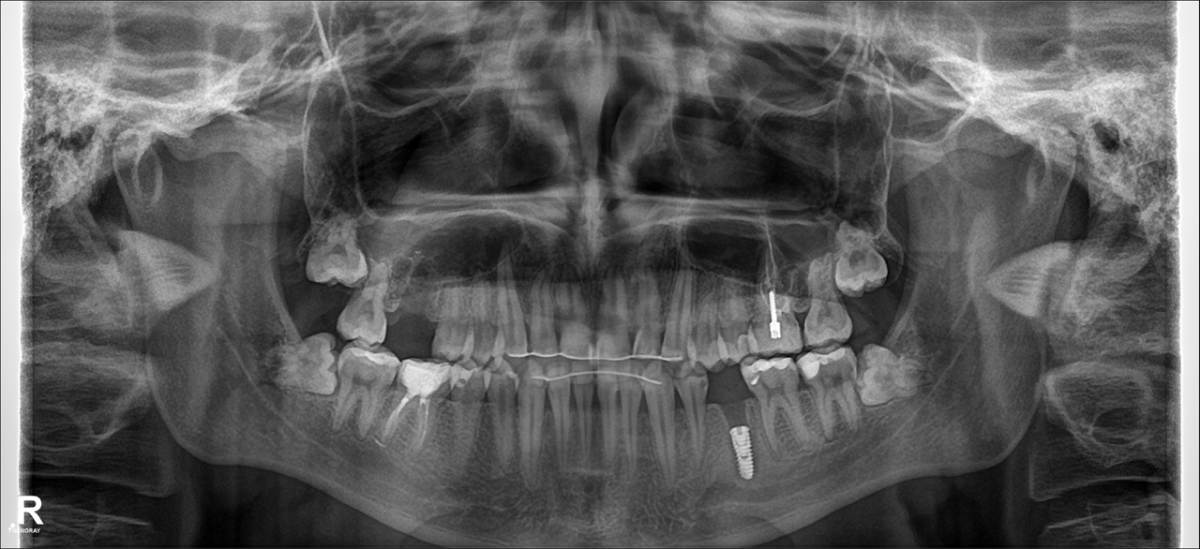

Dimedr Опубликовано 1 час назад Поделиться Опубликовано 1 час назад Добрый день. Вечером заболела верхняя десна, боль отдавала в клык. Опухла щека, утром поехал в клинику, сказали верхний зуб 16, нужно удалять, т.к. там образовался гной , который со слов врача уже проедает кость. И сказали нижний зуб 35, тоже нужно удалить, а то скоро так же заболит, т.к. на корне киста. В итоге удалили оба зуба, в 35 вкрутили штифт. При удалении сказали гноя не было на 16, но кисту на 35 нашли. Решил попросить снимки челюсти, с начала отказывались давать, из-за чего закрались подозрения. На повторном осмотре хирург сказал, все отлично. Но вечером дома обнаружил, что над клыком рядом с 16 зубом, десна вспухла и побелела. Скажите все ли верно сделали ? Для уточнения, год назад снял брекеты. Ссылка на комментарий